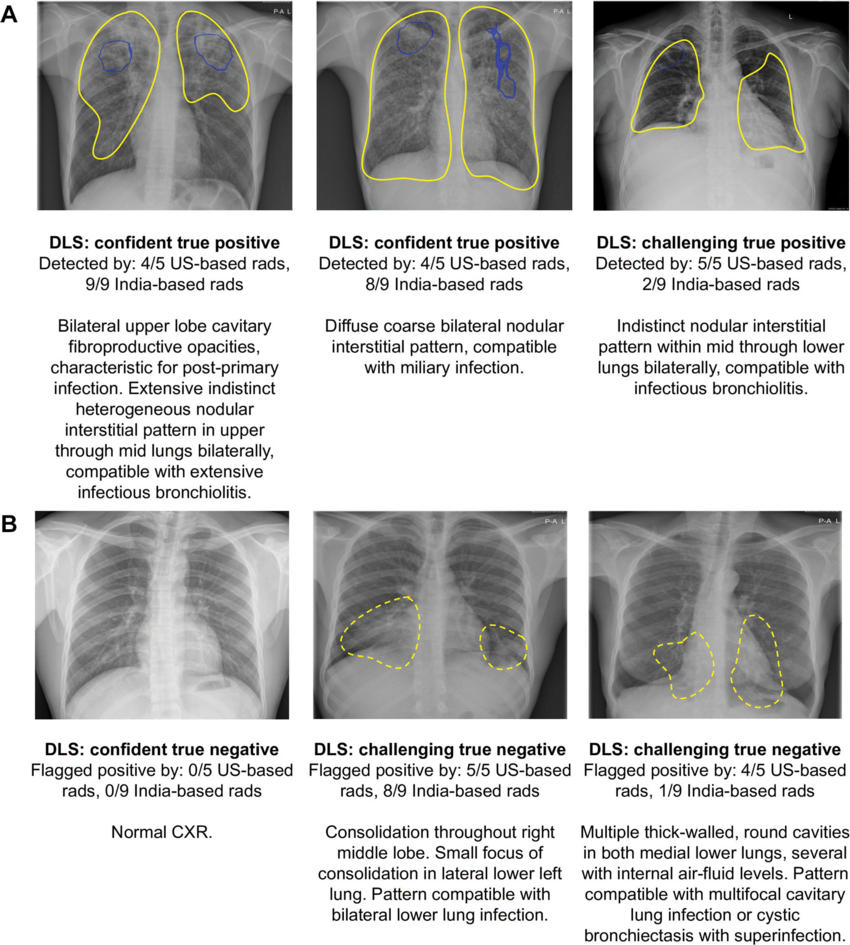

Figure 5. Examples of chest radiographs for which the deep learning system (DLS) provided the correct interpretation, corresponding to (A) tuberculosis (TB)–positive subjects and (B) TB-negative subjects. Blue outlines encircle salient regions via Grad-CAM (35) that most influence the positive prediction from the DLS and are shown when the DLS considered the image positive. Yellow outlines were annotated by a radiologist to indicate regions of interest; solid outlines indicate findings consistent with TB while dotted outlines indicate other findings. “Confident” indicates that the DLS predicted values close to 0 or 1, whereas “challenging” indicates that the DLS predicted values close to the operating point (0.45). CXR = chest radiograph, rads = radiologists